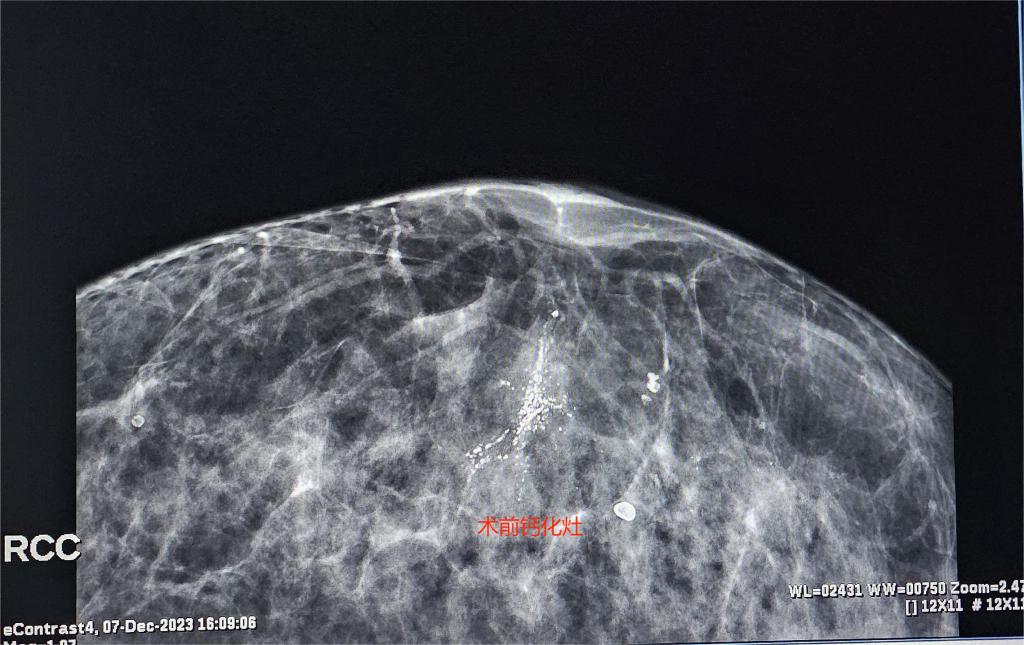

患者女性,57岁,因体检行乳腺X线检查发现“右侧乳腺可疑钙化”,查体后双侧乳腺未触及明显肿块,双侧腋窝未触及肿大淋巴结,复查乳腺X线提示“右乳下象限段样分布细小多形性及粗糙不均质钙化,BI-RADS 4类”,不排除恶性病变。患者入院后科室进行多次术前讨论,决定为患者行Pristina Serena活检机器人三维立体定位下乳腺钙化微创旋切活检术。术中利用X线定位技术,精准找到并成功切除钙化病灶,目前患者恢复良好。

乳腺钙化是乳腺癌常见表现病变之一,及早发现并治疗钙化灶对预防和早期诊断乳腺癌具有重要意义。过去,对于乳腺钙化的治疗主要以开放手术切除为主,但这种方法切除目标不精确、定位困难、创伤范围较大、影响乳房外形、恢复周期长。

乳腺X线Pristina Serena活检机器人,可通过X/Y/Z轴3D评估、立体定位病灶,之后运用微创旋切活检刀,完成病灶切除活检,获取足量病变组织进行病理检查。不仅提高了病变组织切除率,同时最大限度保护了正常组织,具有精准化、创伤小、恢复快、美观度高等优点,为患者提供了更为先进、有效的检查和治疗手段。